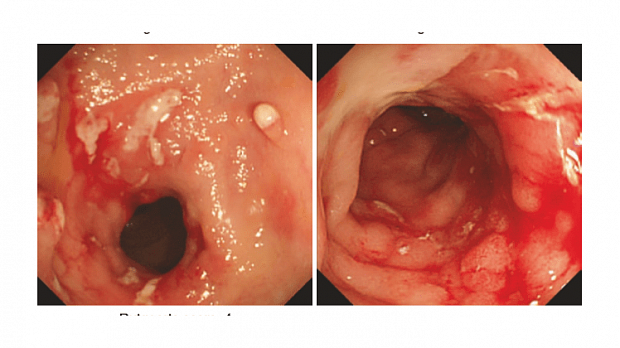

Rutgeerts i0

bolezn_krona.png

Rutgeerts i1

Rutgeerts i2

Rutgeerts i3

Rutgeerts i4

i0

Нет признаков воспаления

i1

≤5 афтозных язв

i2

>5 афтозных язв с нормальной слизистой оболочкой между ними ИЛИ протяженные участки здоровой слизистой оболочки между более выраженными изъязвлениями ИЛИ поражения, ограниченные подвздошно-толстокишечным анастомозом

i3

Диффузный афтозный илеит с диффузно-воспаленной слизистой оболочкой

i4

Диффузное воспаление с крупными язвами, «булыжной мостовой» И/ИЛИ сужением просвета